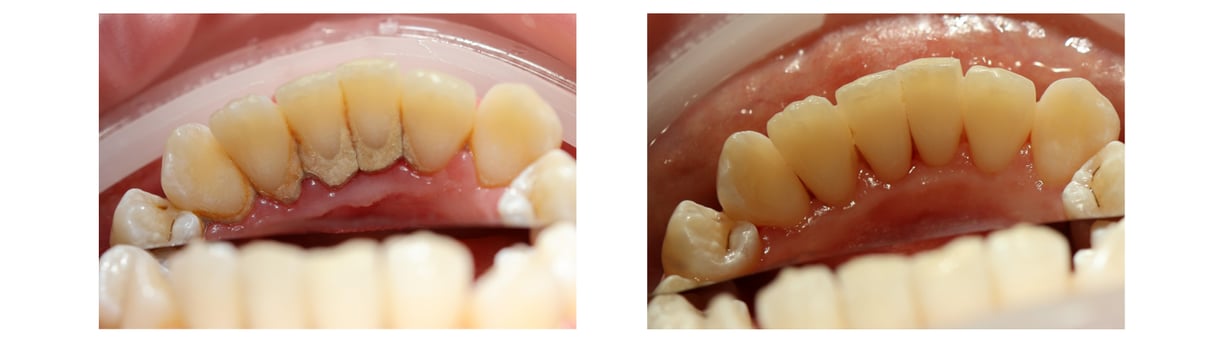

PROFESIONALI BURNOS HIGIENOS PROCEDŪRA

Pacientui buvo alikta profesionali burnos higienos procedūra.

Viso kaina - 70 eur

Gydymo trukmė - 1 valanda

Specialistas - burnos higienistė Justina Šerpytytė